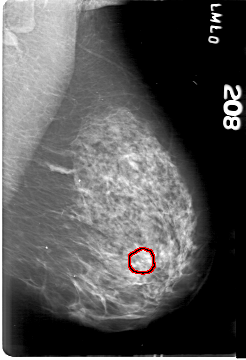

D_4164_1.LEFT_MLO

D_4164_1.LEFT_CC

LEFT_CC LINES 5386 PIXELS_PER_LINE 3871 BITS_PER_PIXEL 12 RESOLUTION 43.5 OVERLAY

LEFT_MLO LINES 5386 PIXELS_PER_LINE 3676 BITS_PER_PIXEL 12 RESOLUTION 43.5 OVERLAY

FILE: D_4164_1.LEFT_MLO.OVERLAY

TOTAL_ABNORMALITIES 1

ABNORMALITY 1

LESION_TYPE CALCIFICATION TYPE AMORPHOUS DISTRIBUTION CLUSTERED

ASSESSMENT 0

SUBTLETY 3

PATHOLOGY BENIGN

TOTAL_OUTLINES 1

BOUNDARY

FILE: D_4164_1.LEFT_CC.OVERLAY